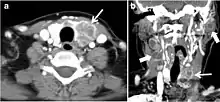

Fig. 9. A 58-year-old male patient with persistence PTC at thyroid bed with hypervascular nodal metastasis. a–c Transverse greyscale and colour Doppler neck ultrasound demonstrate hypoehoic soft tissue in the left thyroid bed (white arrow in a). There are a heterogeneous enlarged lymph nodes at level 2 and 3 with markedly increased vascularity (white arrow in b and c). d–f Enhanced axial CT images of the neck demonstrate a 2.7 × 1.4 cm hypodense soft tissue lesion anterior to the left carotid sheath (white arrow). There are left-sided enhancing abnormal and enlarged lymph nodes at cervical level 2 and 3 (black arrows).[1]